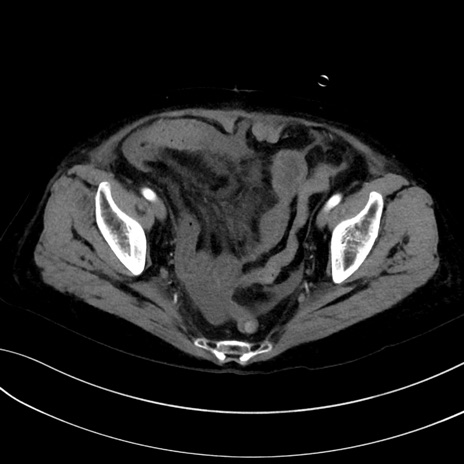

症例13 CT(横断像)1日半後